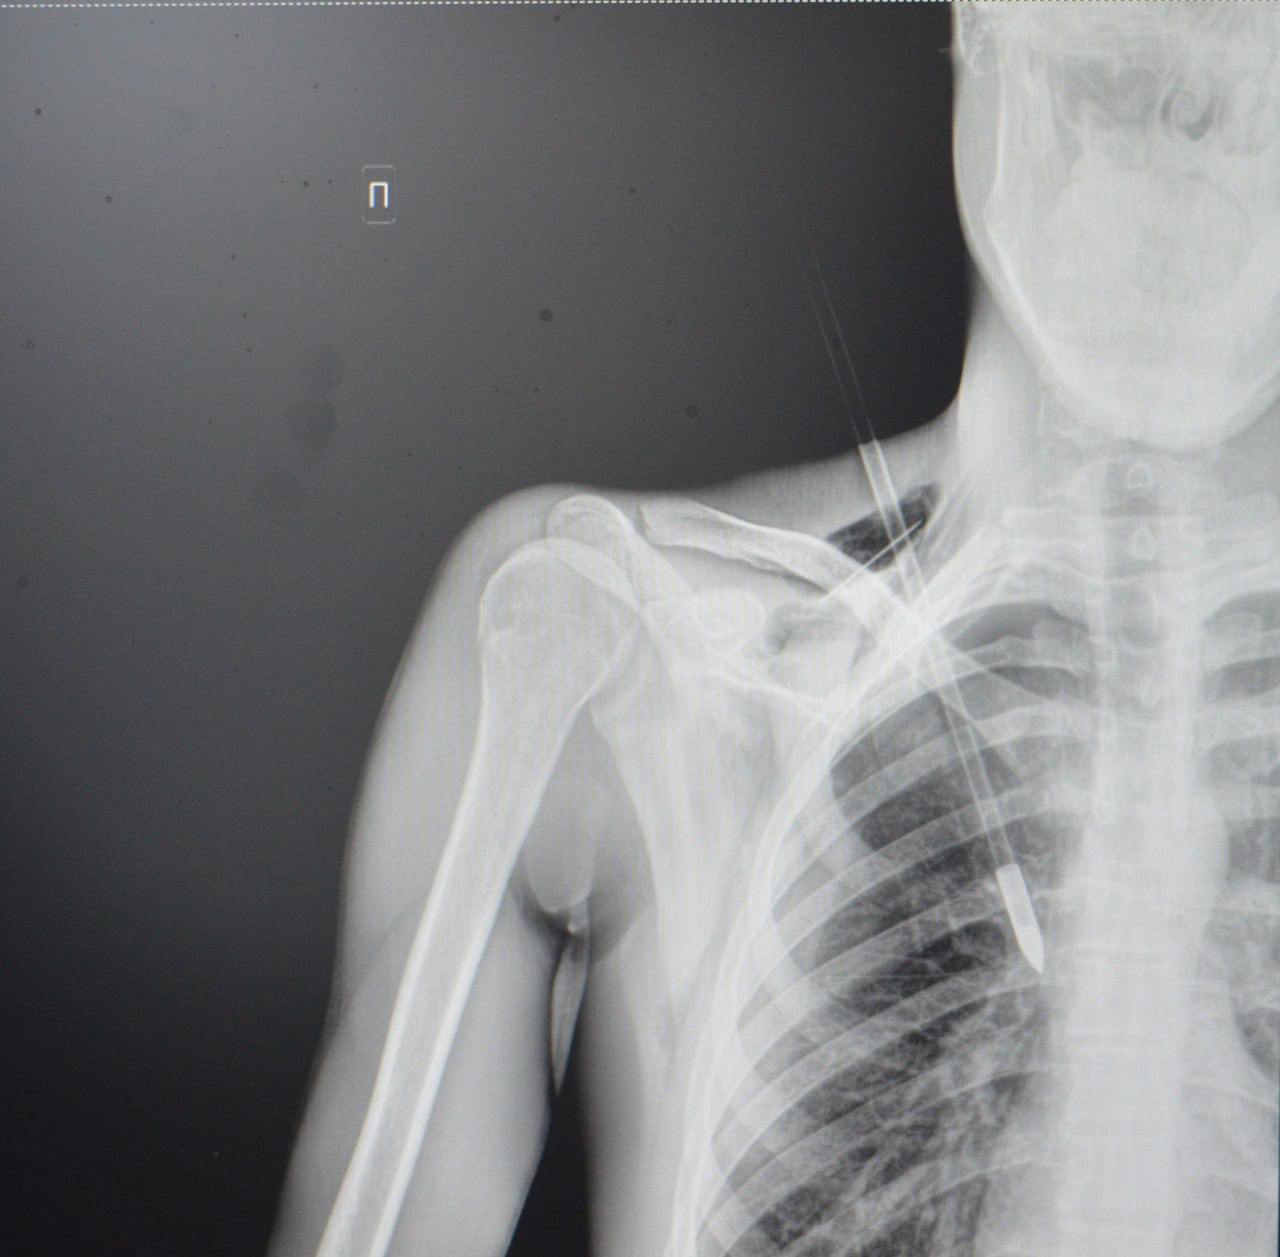

Как рассказали медики, юноша поступил в больницу на скорой со стрелой в грудной клетке. Он рассказал, что вместе с девушкой занимался стрельбой из спортивного лука, когда стрела срикошетила от дерева и вонзилась ему в грудь.

После госпитализации пациента отправили на экстренную операцию: стрела прошла между ключицей и правым ребром, пробив верхушку легкого на шесть сантиметров. По словам врачей, юноше повезло, что предмет не задел подключичную артерию или вену.

«Это привело бы к критическому кровотечению. Такие травмы требуют немедленного хирургического вмешательства. Мы успешно удалили инородное тело, а потом ушили поврежденное легкое и дренировали плевральную полость», — рассказал хирург больницы Тимур Колесников.